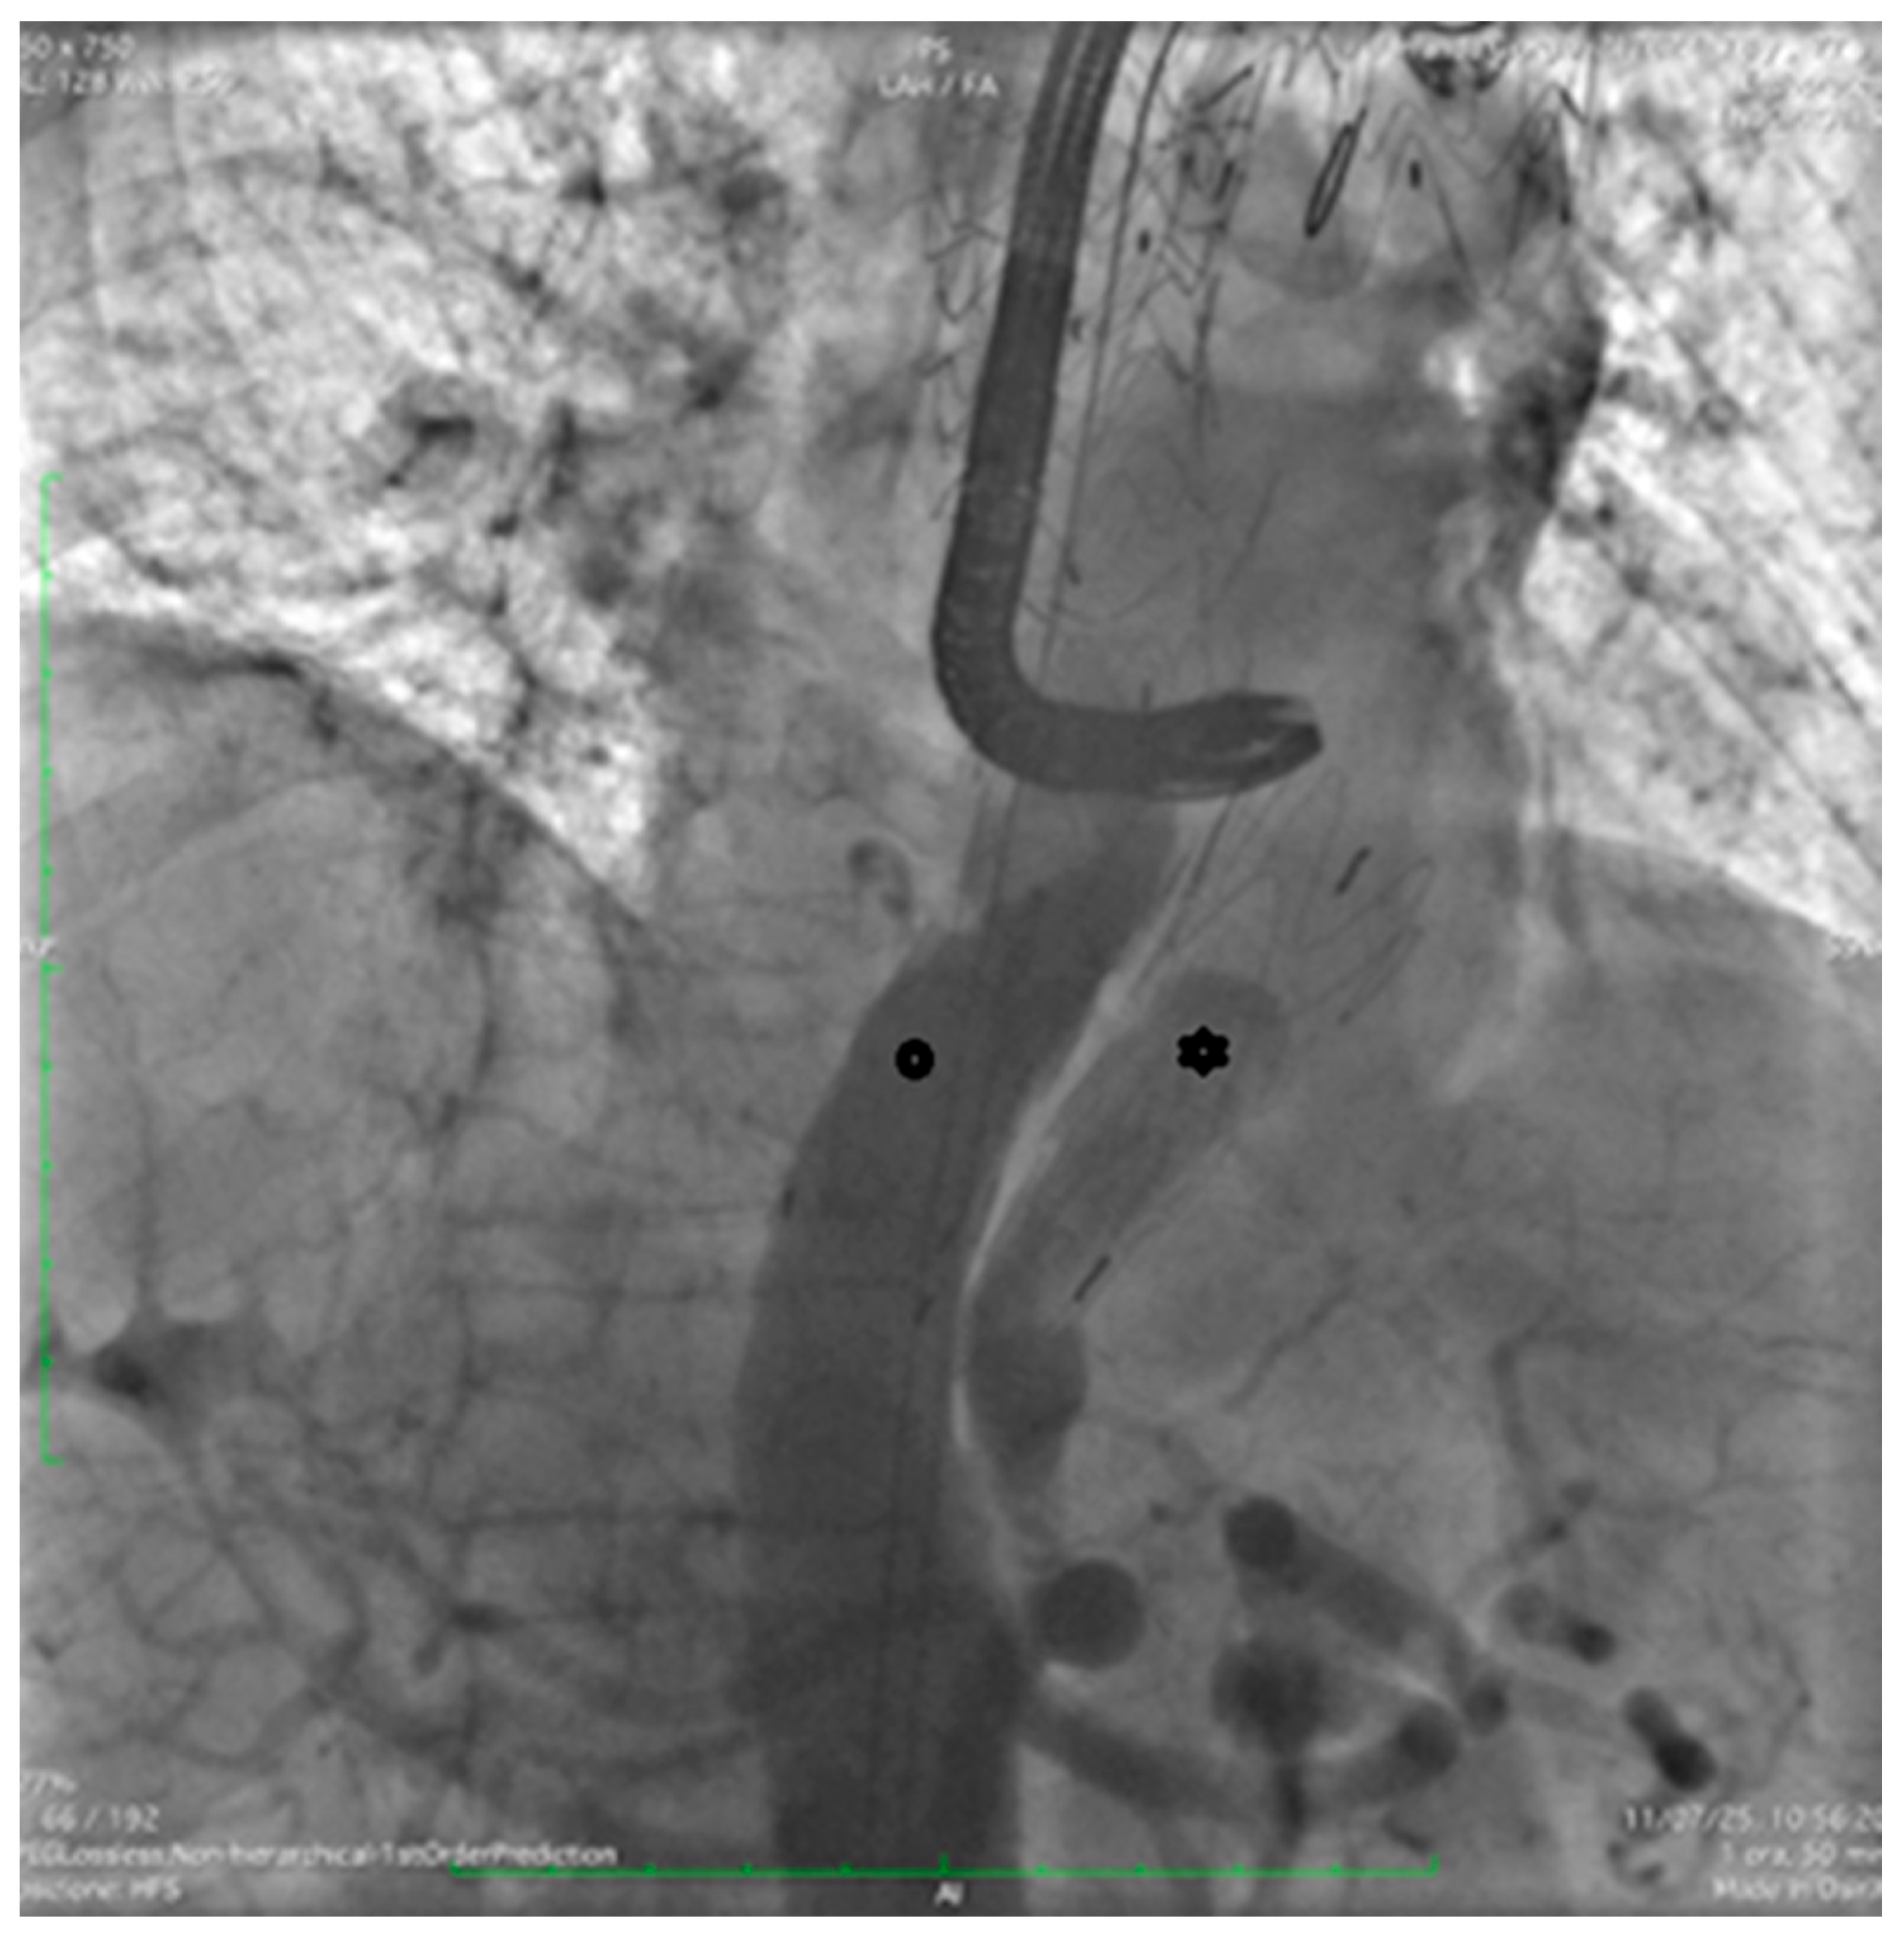

Through the LCFA, a 6F pigtail catheter was advanced into the thoracoabdominal aorta. Intraoperative angiography confirmed substantial FL dilation and two distal re-entry tears beyond the prior TEVAR, with clear retrograde backflow (Figure 2).

Figure 2. Intraoperative angiography with injection into the true lumen demonstrating marked false lumen dilation with evidence of a distal re-entry tear and retrograde backflow (arrow).